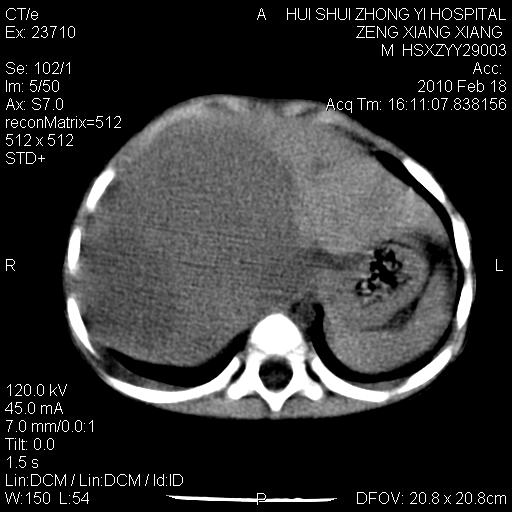

标题: PED3106:男,2岁,腹胀1月。 [打印本页]

标题: PED3106:男,2岁,腹胀1月。

定位腹膜后,肾上腺来源;

定性:恶性神经源性,肾上腺神经节母细胞瘤可能性大。

鉴别:肝母、肾母、肝脏中胚层错构瘤。

依据:年龄、有钙化,肾脏及肝脏受压移位。